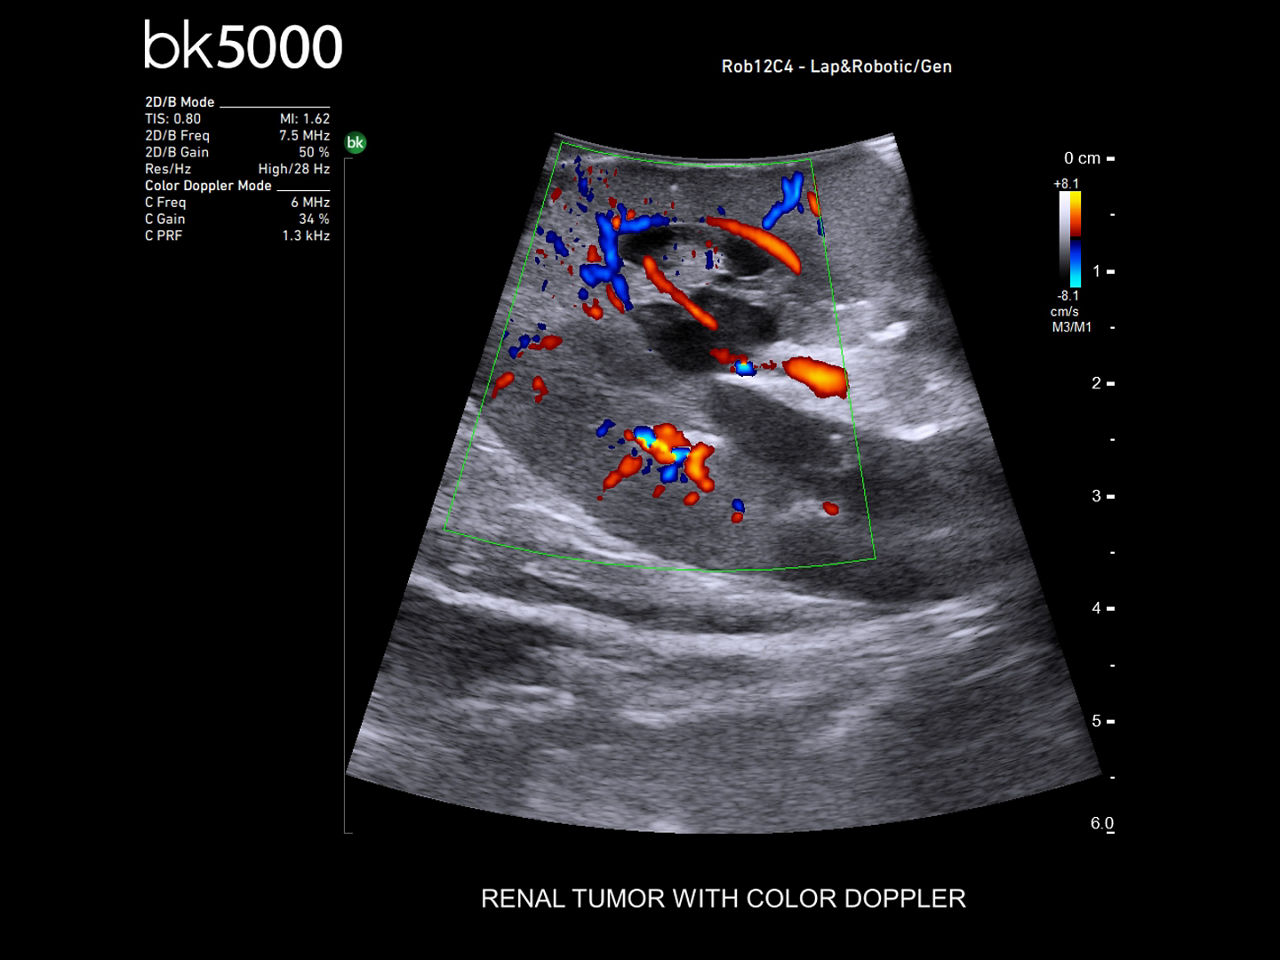

Robotics-assisted surgery with real-time intraoperative ultrasound allows surgeons to precisely locate and visualize anatomical abnormalities. Assess benign and malignant lesions, key arteries, veins, and other structures with high-resolution active imaging for enhanced surgical outcomes.